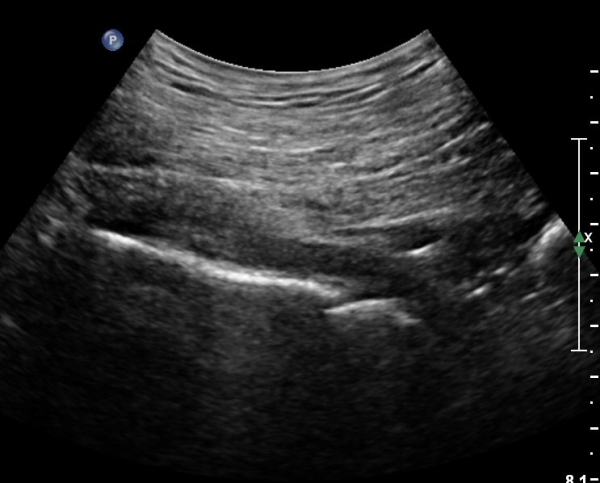

ŽÃÍÀÚ¸¦ ´Ù¸®ÂÊÀ¸·Î ¼öÆò À̵¿ÇÏ¸é ½ÉÃþ¿¡¼­ Àå°ñÀÌ »ç¶óÁö°í »õ·Î¿î ±ÙÀ°ÃþÀÌ º¸À̴µ¥ À̰ÍÀÌ ÀÌ»ó±ÙÀ̰í ÀÌ»ç±Ù ½ÉÃþ¿¡¼­ Á°ñ½Å°æ¸£ °üÂûÇÒ ¼ö ÀÖ´Ù(»çÁø 2, 3).